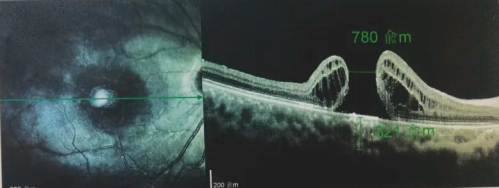

由于自身患有頸椎病,每次術(shù)后長期的趴睡都讓他痛苦不堪。為了尋求更好的治療,吳爺爺來到廈門大學(xué)附屬廈門眼科中心,找到了眼外傷及眼底病2科的李海波博士后。此時(shí),吳爺爺右眼的黃斑裂孔已經(jīng)持續(xù)擴(kuò)大到780μm,演變?yōu)殡y治性的大裂孔。

最讓吳爺爺難以置信的是:術(shù)后只需保持平躺24小時(shí)!第二天復(fù)查時(shí),眼底鏡及OCT檢查清晰顯示——那個(gè)折磨了他大半年的大裂孔,竟然閉合了!且吳爺爺?shù)挠已垡暳τ辛嗣黠@的改善,術(shù)后3天已經(jīng)可以看到 0.15。

黃斑裂孔